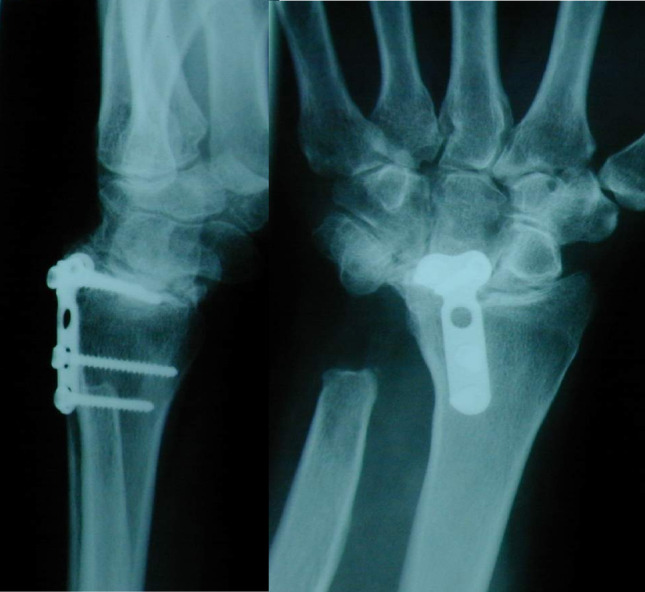

Patients/materials/methods: Between 2000 and 2011, a total of 29 total endoprostheses were implanted in 25 patients in a single centre study due to severe degenerative changes in the wrist. Of these, 22 had rheumatoid arthritis and 3 degenerative osteoarthritis. The prosthesis models BIAX (N = 13) and Universal II (N = 16) were implanted. The present study describes the mean outcome after a mean observation period of 13.8 (1.7-21.4) years for the BIAX prosthesis and 10.5 years (0.2-16.4) for the Universal II prosthesis.

Results: The probability of survival after 15 years is 60% for the BIAX prosthesis and 41% for the Universal II prosthesis. After 21 years, results are only available for the BIAX prosthesis with a value of 60%. The BIAX prosthesis showed a lower complication rate. Subjectively, 15 years postoperatively, the BIAX prosthesis showed a lower mean value in the QuickDASH score (BIAX 33.8%, Universal II 50.3%), lower results in the visual analogue pain scale under stress (BIAX: 1 point; Universal II: 3 points) with higher patient satisfaction (BIAX: 86%; Universal II: 78%).